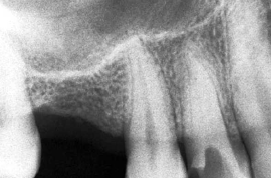

5- Lesiones periodontales como perdida ósea vertical y lesiones de

furca en multirradiculares, concomitantes con alteración pulpar.

Este tipo de lesiones deben ser evaluadas como parte de un

proceso de deterioro pulpo-periodontal concomitante o no.

Es sabido que lesiones periodontales afectan la biología pulpar,

llevando a un proceso de necrosis pulpar. Y que lesiones pulpares

del tipo necrótico producen manisfestaciones en la lámina

periodontal. (lesion de furcación)

La radiografía periapical es un elemento valioso para detectar

este tipo de lesiones, por su nivel de detalle ,contraste y bajo

costo.